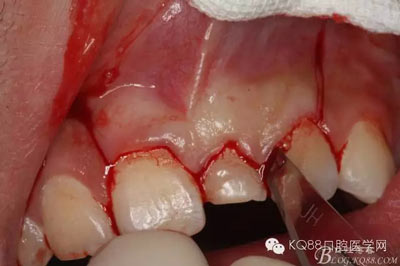

圖4.腭側(cè)觀(guān):左乳Ⅰ腭側(cè)牙齦正常,無(wú)松動(dòng),擬摘除牙瘤,暫時(shí)保留左乳Ⅰ。